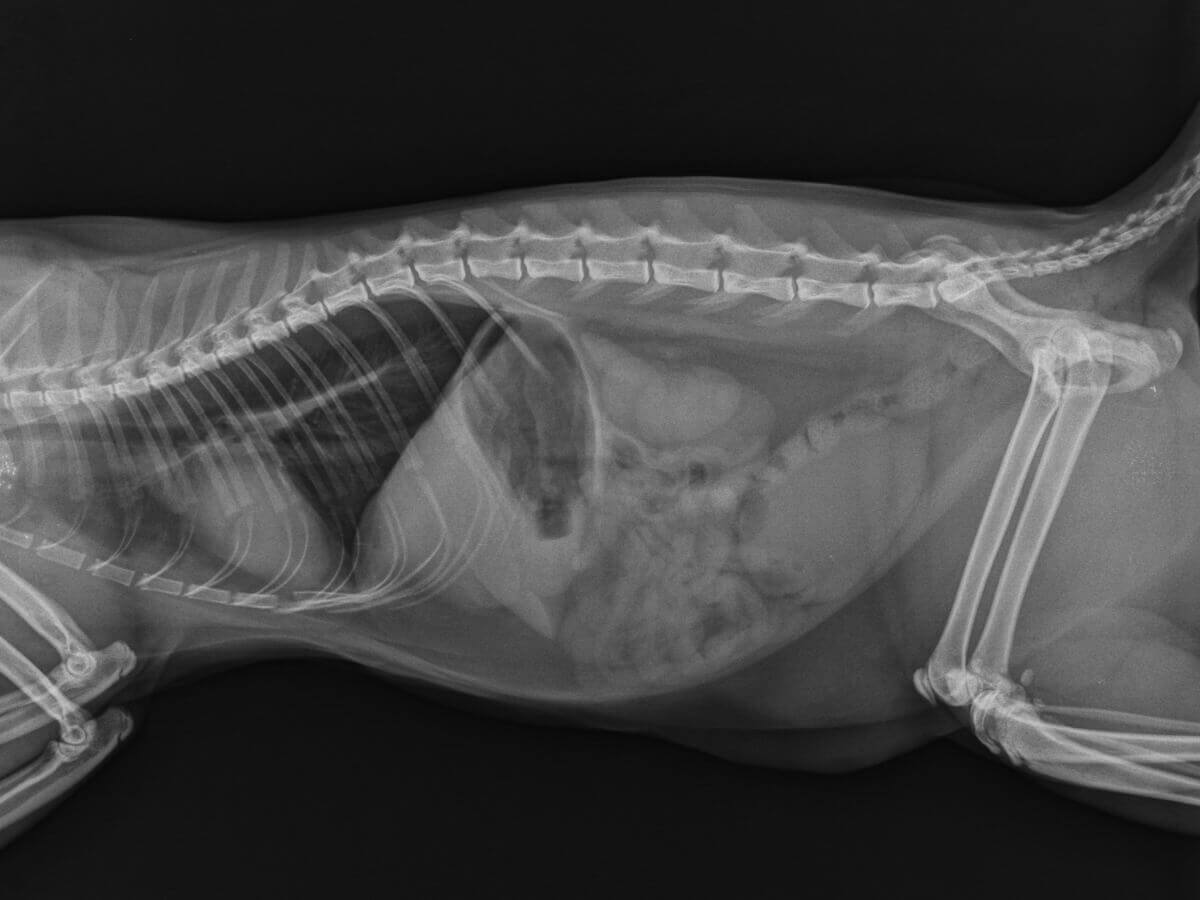

Uma vez na clínica, o profissional irá suspeitar dos urólitos a partir dos sinais do animal ou após palpação direta. Se um cristal for detectado, vários exames de imagem serão necessários para confirmar o diagnóstico. Os raios-X detectam urólitos de até 3 milímetros de diâmetro, mas outras técnicas de imagem, como o ultrassom, também podem ser úteis.